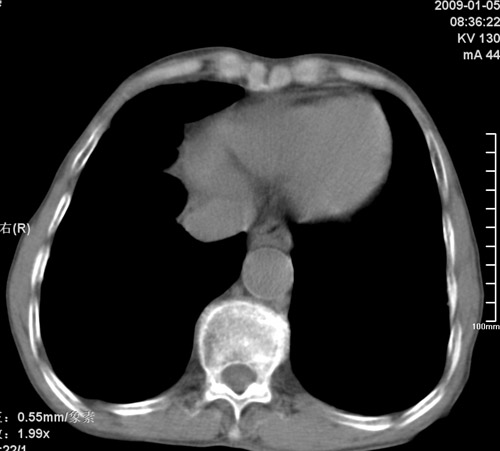

标题: CT17529:男 76 胸背部不适半月 胸透支气管炎 行CT检查 [打印本页]

标题: CT17529:男 76 胸背部不适半月 胸透支气管炎 行CT检查

意见 老年肺 少许炎症 肺大泡 右肺门略大 但支气管通畅  请各位高手指教如何下意见

间质纤维化伴少许炎症!另:肺大泡形成!

支持楼主意见,右肺门略大,可能为肺动脉增粗.

慢支肺气肿,肺动脉高压.